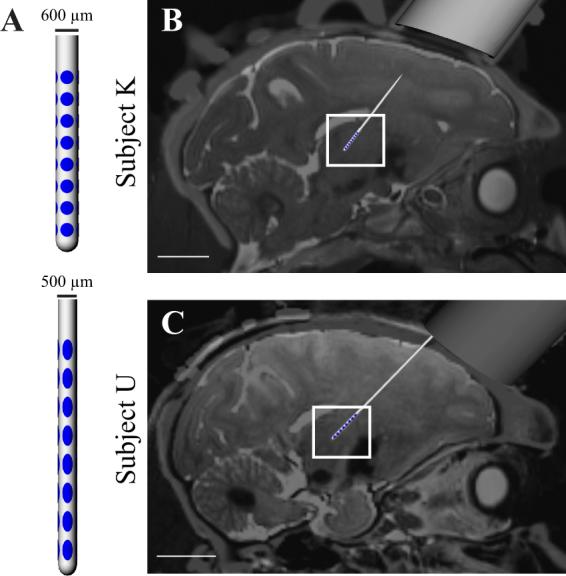

Deep brain stimulation (DBS) therapy is a potent tool for treating a range of brain disorders. High frequency stimulation (HFS) patterns used in DBS therapy are known to modulate neuronal spike rates and patterns in the stimulated nucleus; however, the spatial distribution of these modulated responses are not well understood. Computational models suggest that HFS modulates a volume of tissue spatially concentrated around the active electrode. Here, we tested this theory by investigating modulation of spike rates and patterns in non-human primate motor thalamus while stimulating the cerebellar-receiving area of motor thalamus, the primary DBS target for treating Essential Tremor. HFS inhibited spike activity in the majority of recorded cells, but increasing stimulation amplitude also shifted the response to a greater degree of spike pattern modulation. Modulated responses in both categories exhibited a sparse and long-range spatial distribution within motor thalamus, suggesting that stimulation preferentially affects afferent and efferent axonal processes traversing near the active electrode and that the resulting modulated volume strongly depends on the local connectome of these axonal processes. Such findings have important implications for current clinical efforts building predictive computational models of DBS therapy, developing directional DBS lead technology, and formulating closed-loop DBS strategies.